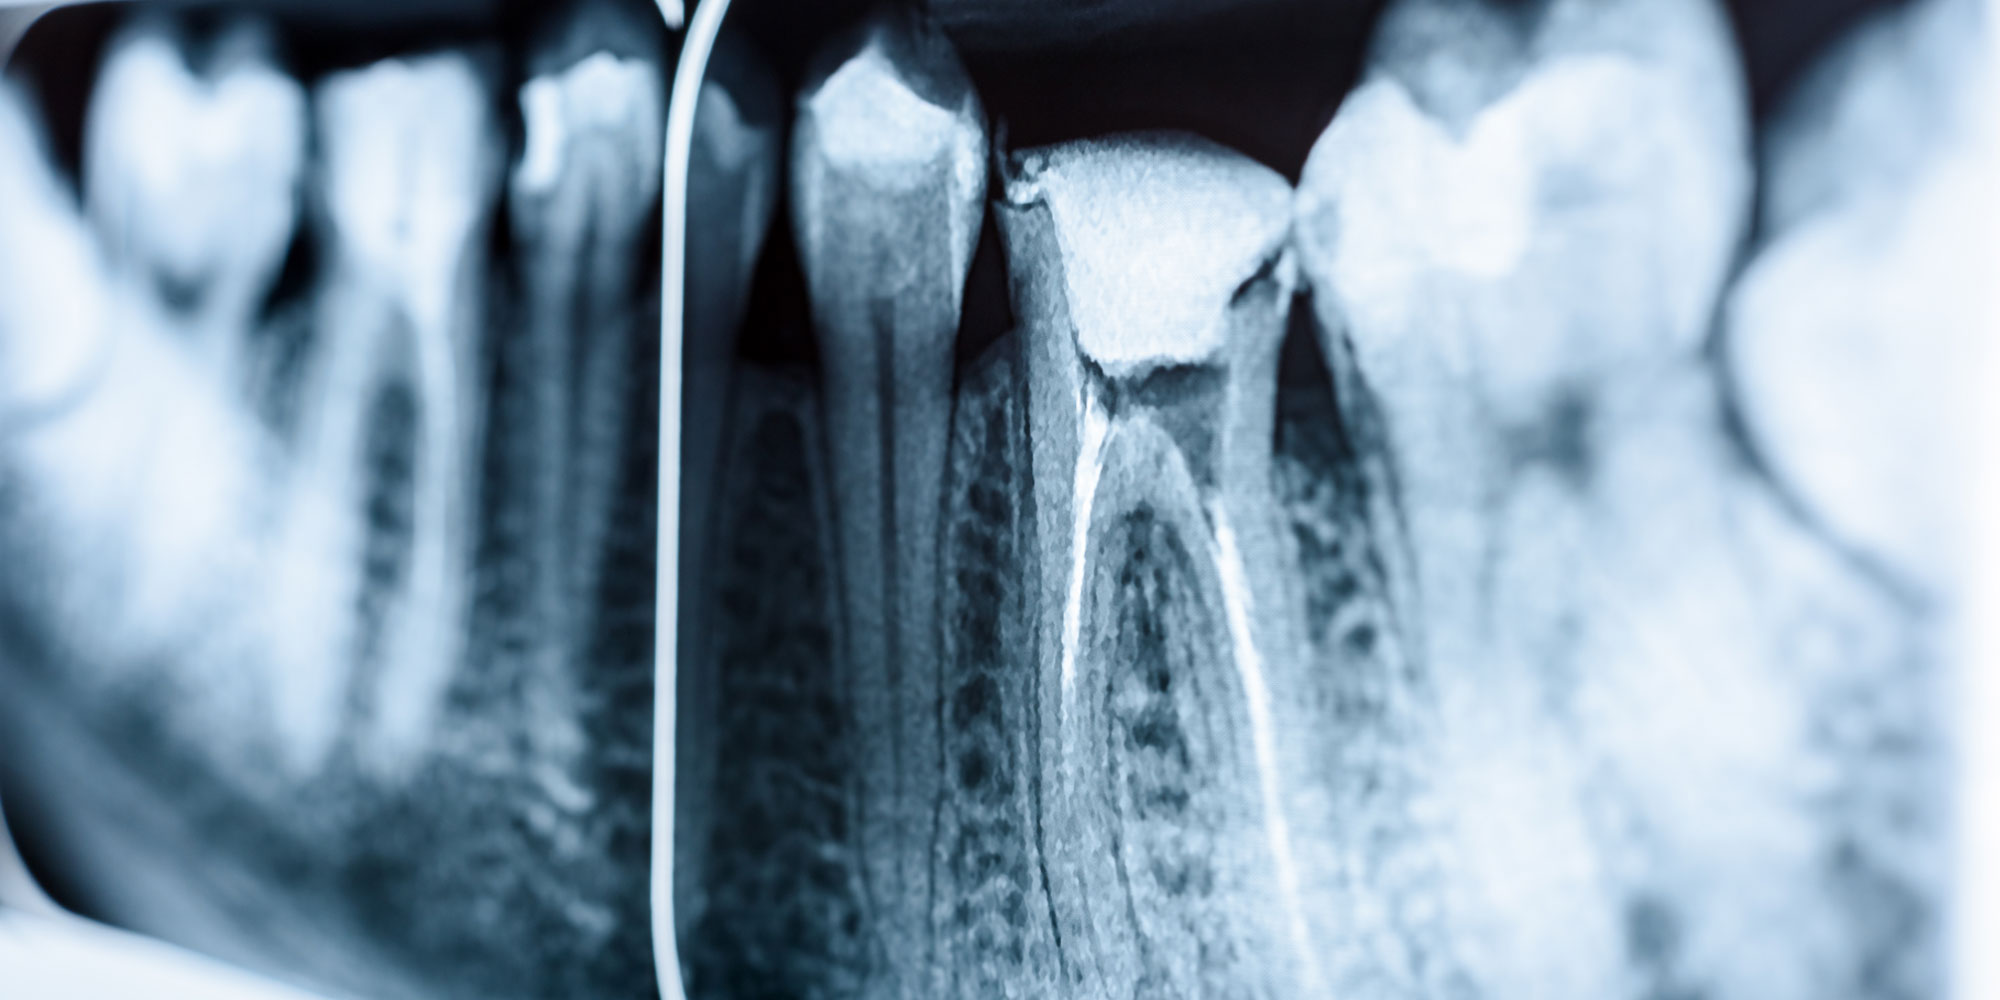

The Out-of-Sight, Essential Tooth Root

A tooth root comprises the lower two-thirds of your tooth and serves as its anchor, maintaining the health of your jawbone. The radicular portion of the tooth, located below the pulp chamber, houses the root canal space. The apex, the tip of the tooth root, can be round, oval, long oval, flattened, or irregular. Incisors, canines, and premolars typically have a single root, while molars have two or three, each of which can become infected.

When pulp inside your tooth root becomes infected, it’s crucial to remove the pulp and bacteria to save your tooth, maintain good oral health, and overall well-being. During a root canal in South Elgin, IL, our oral surgeon begins by numbing the treatment site with a local anesthetic, ensuring you won’t feel any pain, although you may experience slight pressure during the procedure. Next, we drill a small hole in your tooth crown to access the pulp chamber. Carefully, we remove all the bacteria, infected pulp, and tissues. Then, we fill and seal the end of the tooth with a rubberlike material called gutta-percha. Finally, we restore the tooth with a crown or filling to protect it and restore its normal function. We accept various insurance plans and offer third-party financing options to ensure your treatment is both painless and affordable.